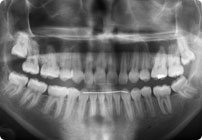

Galería

Femenino

Antes

Despues

Caso: 12 años

Adolescente: Clase II

Dental Maxilar Protrusion

Extract U4’s/L5’s

4 series de alambres:

.016″, 022″, .0215″ x .028″, .019″ x .025″ Trenzado

Elástico clase 2 2oz. TP amarillos y verdes

Retenedores: Interior Fijo de TMA y Hawley en superior

Tiempo de tratamiento: 15 Visitas